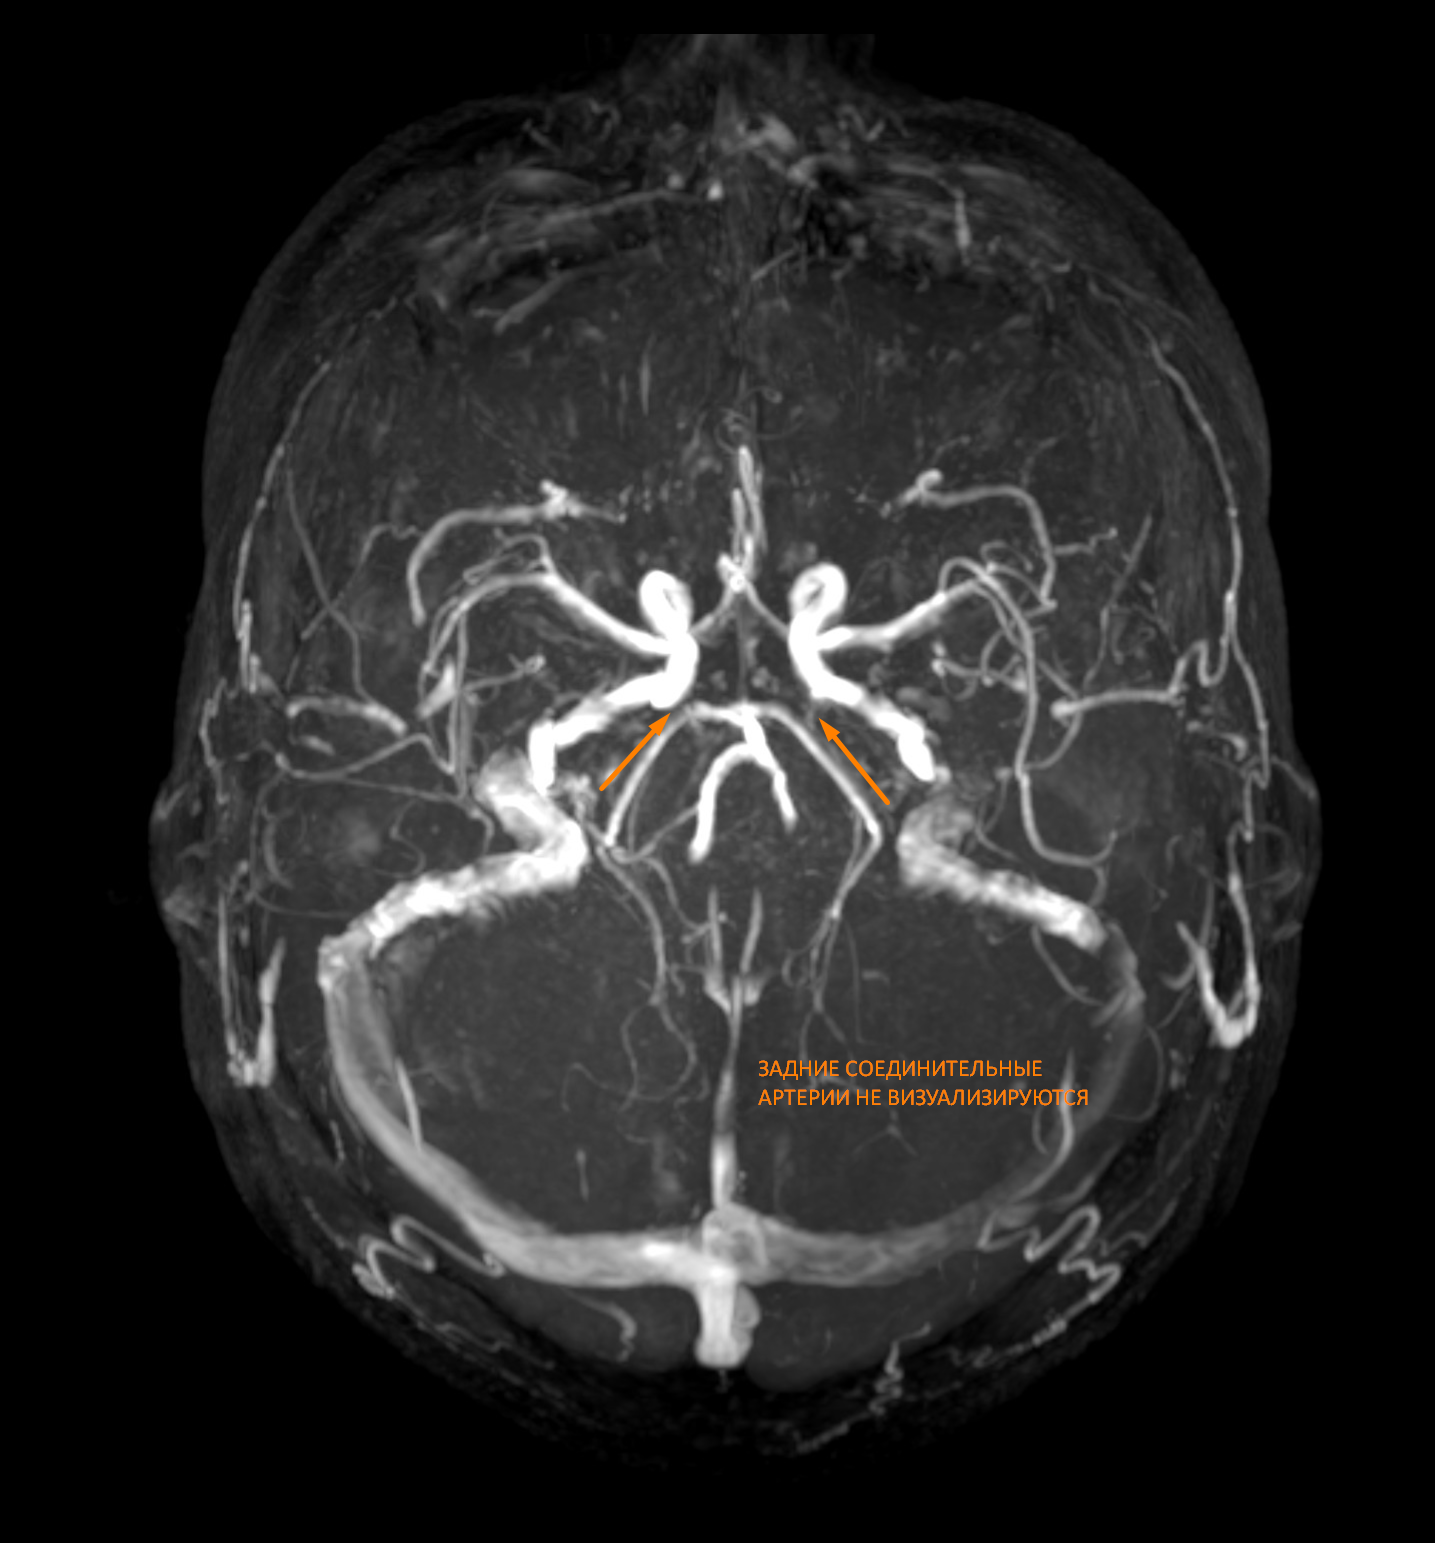

На МР-ангиограммах: cигнал от кровотока по позвоночным артериям симметричный: около 3,5 мм. Ход позвоночных артерий типичный. Сигнал от кровотока по внутренним сонным артериям (ВСА) симметричный: около 4,5 мм. Ход ВСА не изменен. Базилярная артерия имеет типичный ход, просвет равномерный. Виллизиев круг симметричен: выявлена передняя соединительная артерия, кровоток по задним соединительным артериям не визуализируется - вариант развития. Венозный отток сохранен, сигнал от кровотока по поперечным и сигмовидным синусам минимально асимметричный (c доминированием справа).

2.МР-картина незамкнутого Виллизиева круга.

Виллизиев круг состоит из передней и задних соединительных артерий, начальные сегменты передней и задней мозговых артерий, супраклиновидного сегмента внутренней сонной артерии.

Пояснение: В данном случае кровоток по задним соединительным артериям не визуализируется, что является вариантом развития (см. рис.2.).